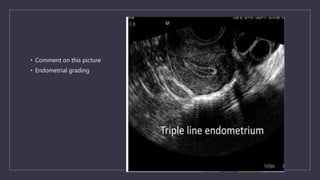

• Comment on this picture

• Endometrial grading

• Gonen and casper in 1990.

• Type a: entirely homogeneous, hyperechogenic pattern, without a central echogenic line

• Type b: intermediate iso-echogenic pattern, with the same reflectivity as the surrounding myometrium and a non-

myometrium and a non-prominent or absent central echogenic line

• Type c: multilayered ‘triple-line’ endometrium consisting of a prominent outer and central hyperechogenic line and inner

hyperechogenic line and inner hypo-echogenic or black region

• APPLEBAUM SCORING

• The endometrial and periendometrial areas are divided into the following four zones

• Zone 1: A 2-mm thick area surrounding the hyperechoic outer layer of the endometrium.

• Zone 2: The hyperechoic outer layer of the endometrium.

• Zone 3: The hypoechoic inner layer of the endometrium.

• Zone 4: The endometrial cavity.